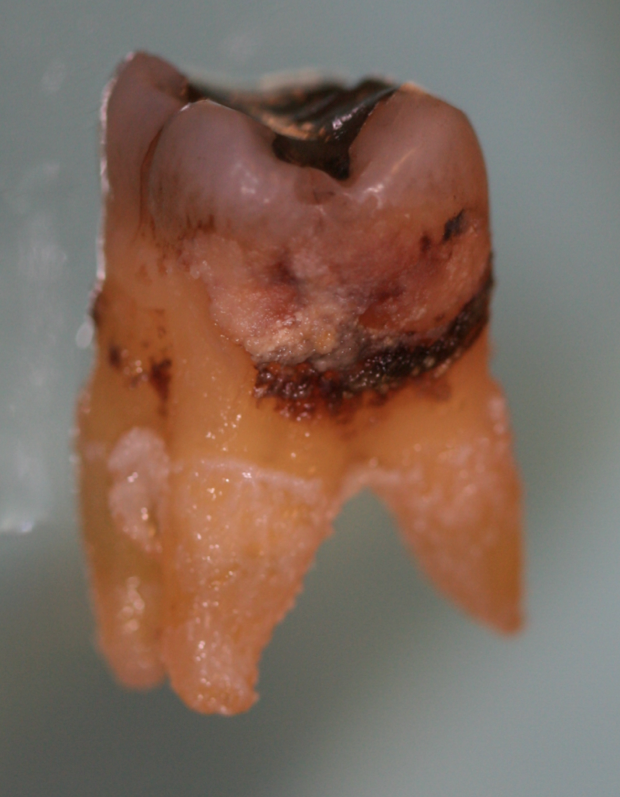

The takeaway of this discussion is that clinicians can no longer take a now-you-see-it—or feel it—approach to periodontal debridement therapy. They should assume that microscopic biofilm covers the entire surface at a site where persistent inflammation is present (Figure 6). At those problem sites, removal of just the visible calculus may not be sufficient. And now, with the advent of the understanding that persistent inflammation has ramifications outside of the mouth, it is important to not only remove the visible and tactile calculus but also the remaining root surface using a method that enables the hygienist to interrupt any potential microscopic etiology and to do it without excessive cementum removal in order to maximize the chance for resolution.

Fig. 6 Practitioners should assume that microscopic biofilm covers the entire surface at a site where persistent inflammation is present. Removal of just the identifiable calcified debris may not be sufficient to return the site to health.

Figure 6